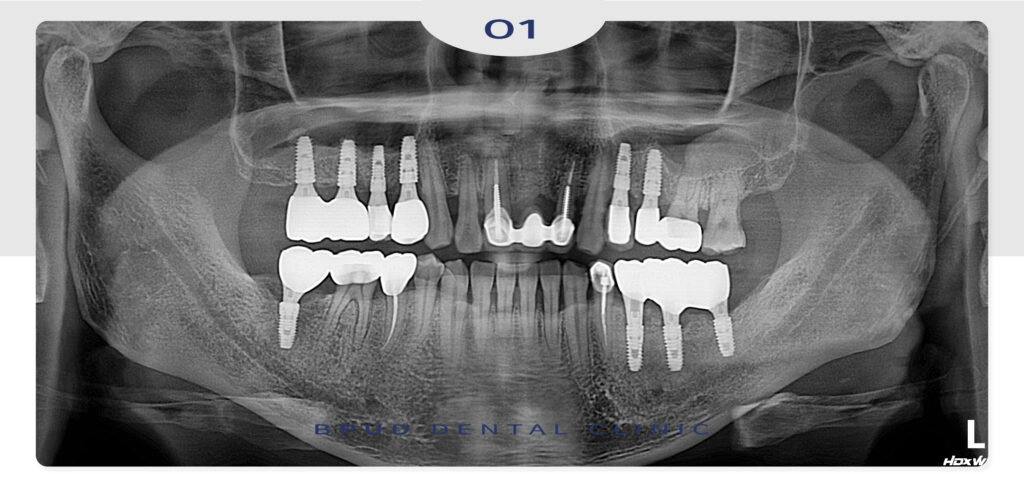

24.11.18

마지막으로 오른쪽 아래 타원 임플란트

보철의 재제작과 앞쪽 어금니까지

크라운 재수복을 마쳤는데요.

환자분께서는 난이도가 높은 치료였지만

잘 마무리가 되어 만족하셨습니다.

22.12.31